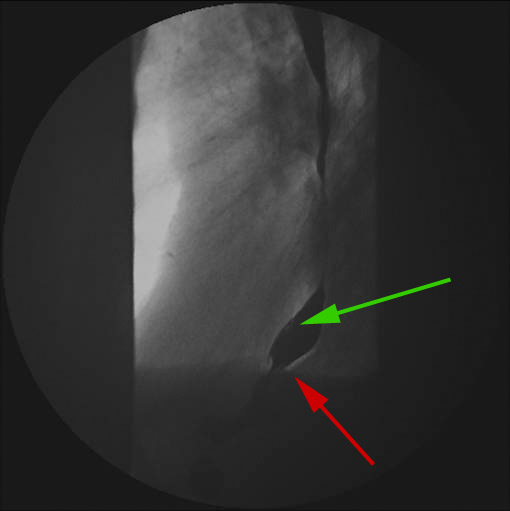

Nederste del af øsofagus med kontrast optaget forfra og fra siden (nederste billede)